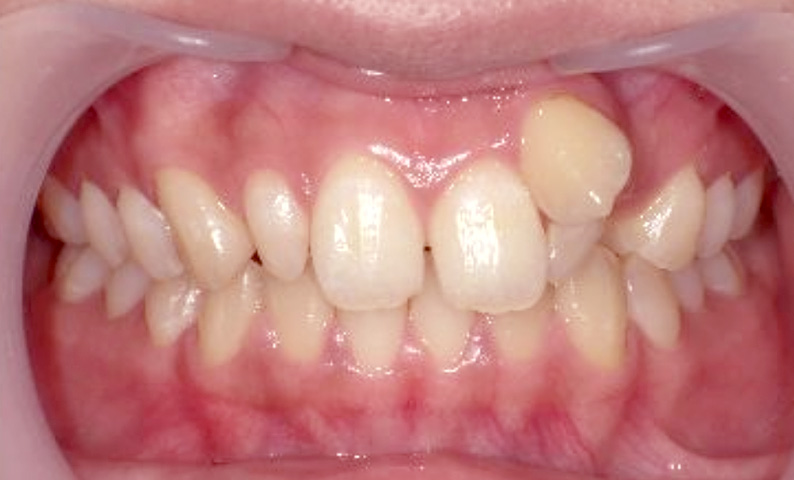

症例_021 上顎だけの部分矯正

治療期間:8ヶ月金額:30万円+税女性前歯のガタガタ八重歯上の前歯だけ

| Before | After |